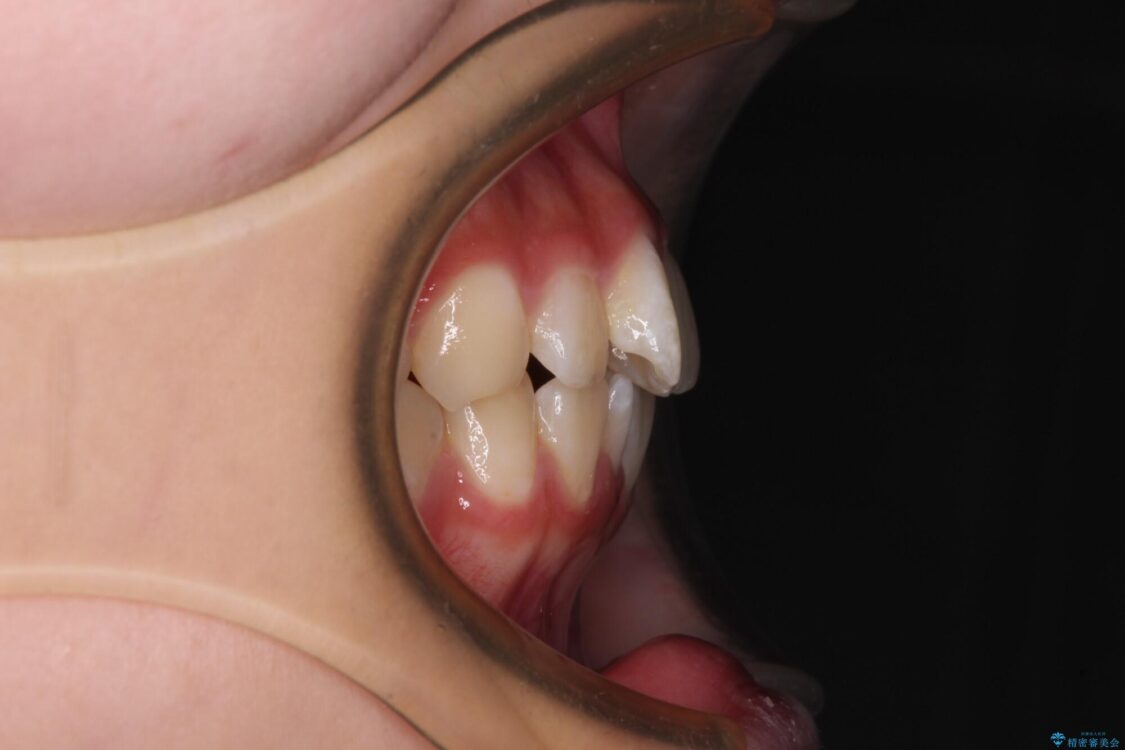

治療前

• インビザラインは使える自信がない ワイヤー装置にて矯正治療 治療前画像